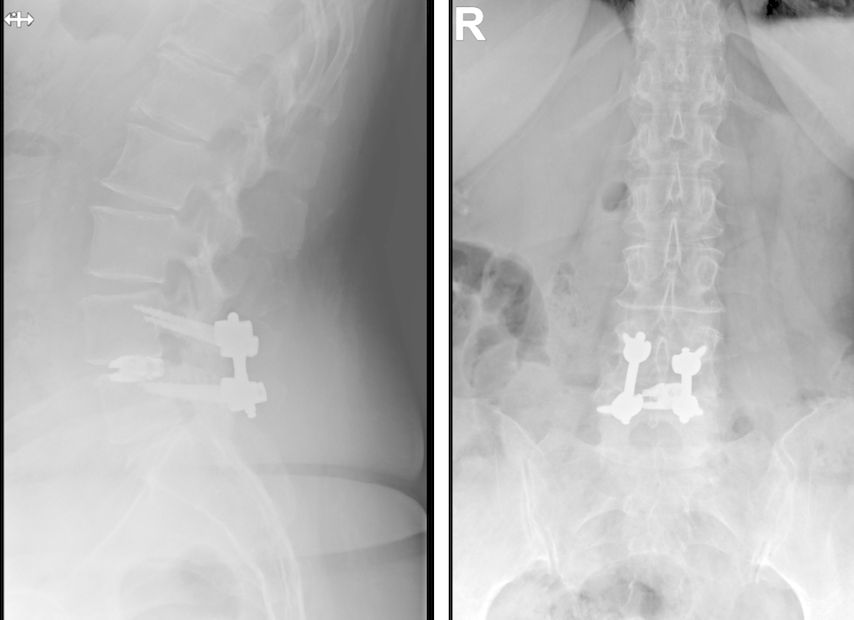

Fallbeispiel 2

TLIF über Mittellinienzugang mit Schrauben in „cortical bone trajectory“. Bei der 63-jährigen Patientin bestand eine degenerative Spondylolisthese Meyerding Grad I mit Facettengelenkszysten und Wirbelkanalstenose (Abb. 8). Klinisch bestanden Lumboischialgien mit Ausstrahlung dem Dermatom L5 bds. entsprechend. Es wurde ein Mittellinienzugang durchgeführt und zuerst wurden navigierte Schrauben in „cortical bone trajectory“ platziert (Abb. 9). Anschließend erfolgten eine Facettektomie L4/5 links und eine Dekompression des Wirbelkanals. Abbildung 10 zeigt, dass der Hautschnitt aufgrund der mittelliniennahen Schraubenköpfe klein gehalten werden kann. Klinisch wurden die lumbalen Schmerzen wie ausstrahlende Beschwerden 1 Jahr postoperativ annähernd vollständig behoben, die korrespondierende Röntgenkontrolle ist in Abbildung 11 dargestellt.